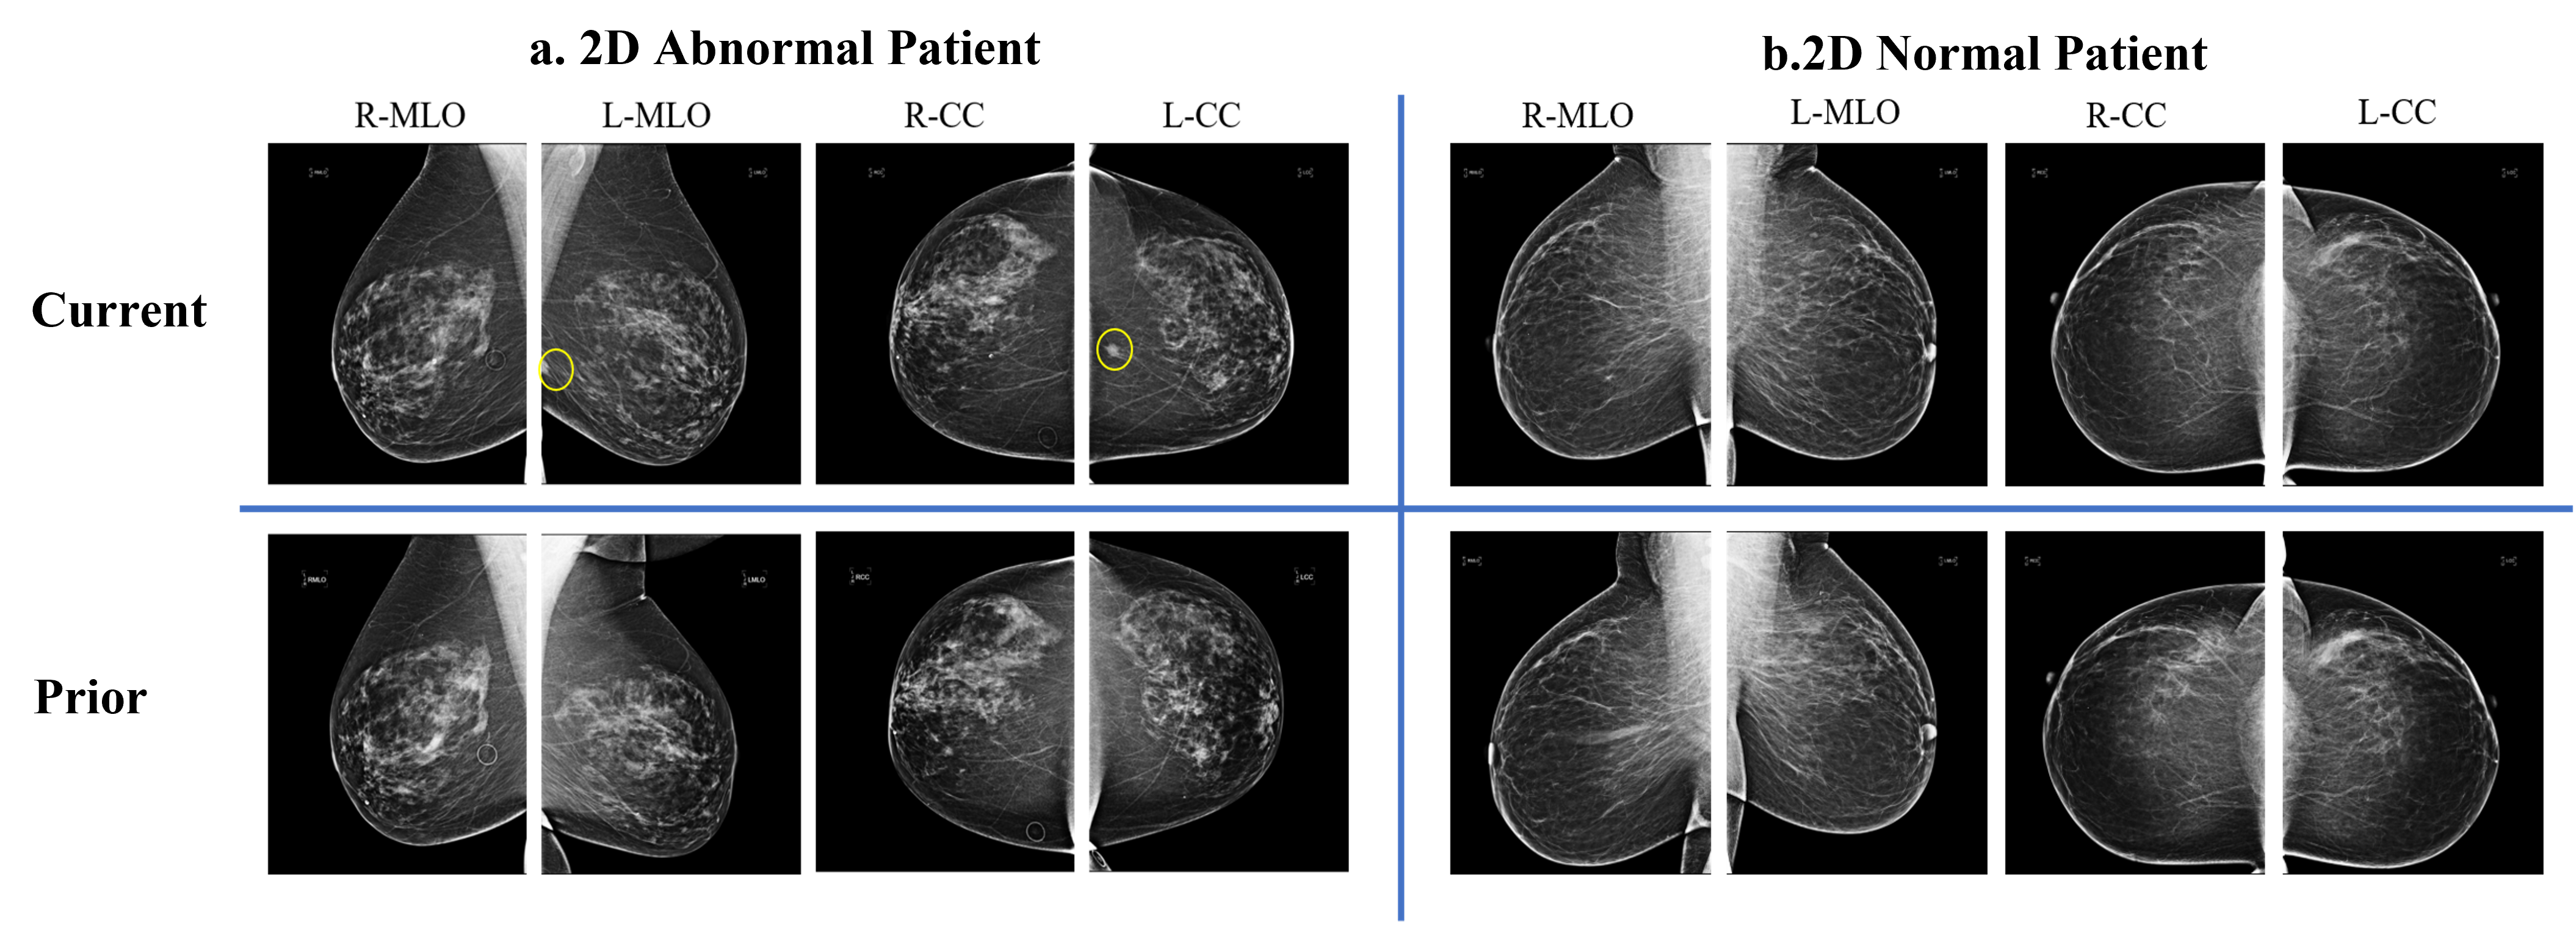

Refer to caption

Figure 3: Examples of current and prior mammograms of a. an abnormal patient and b. a normal patient from our dataset. The yellow circle indicate the abnormal location.